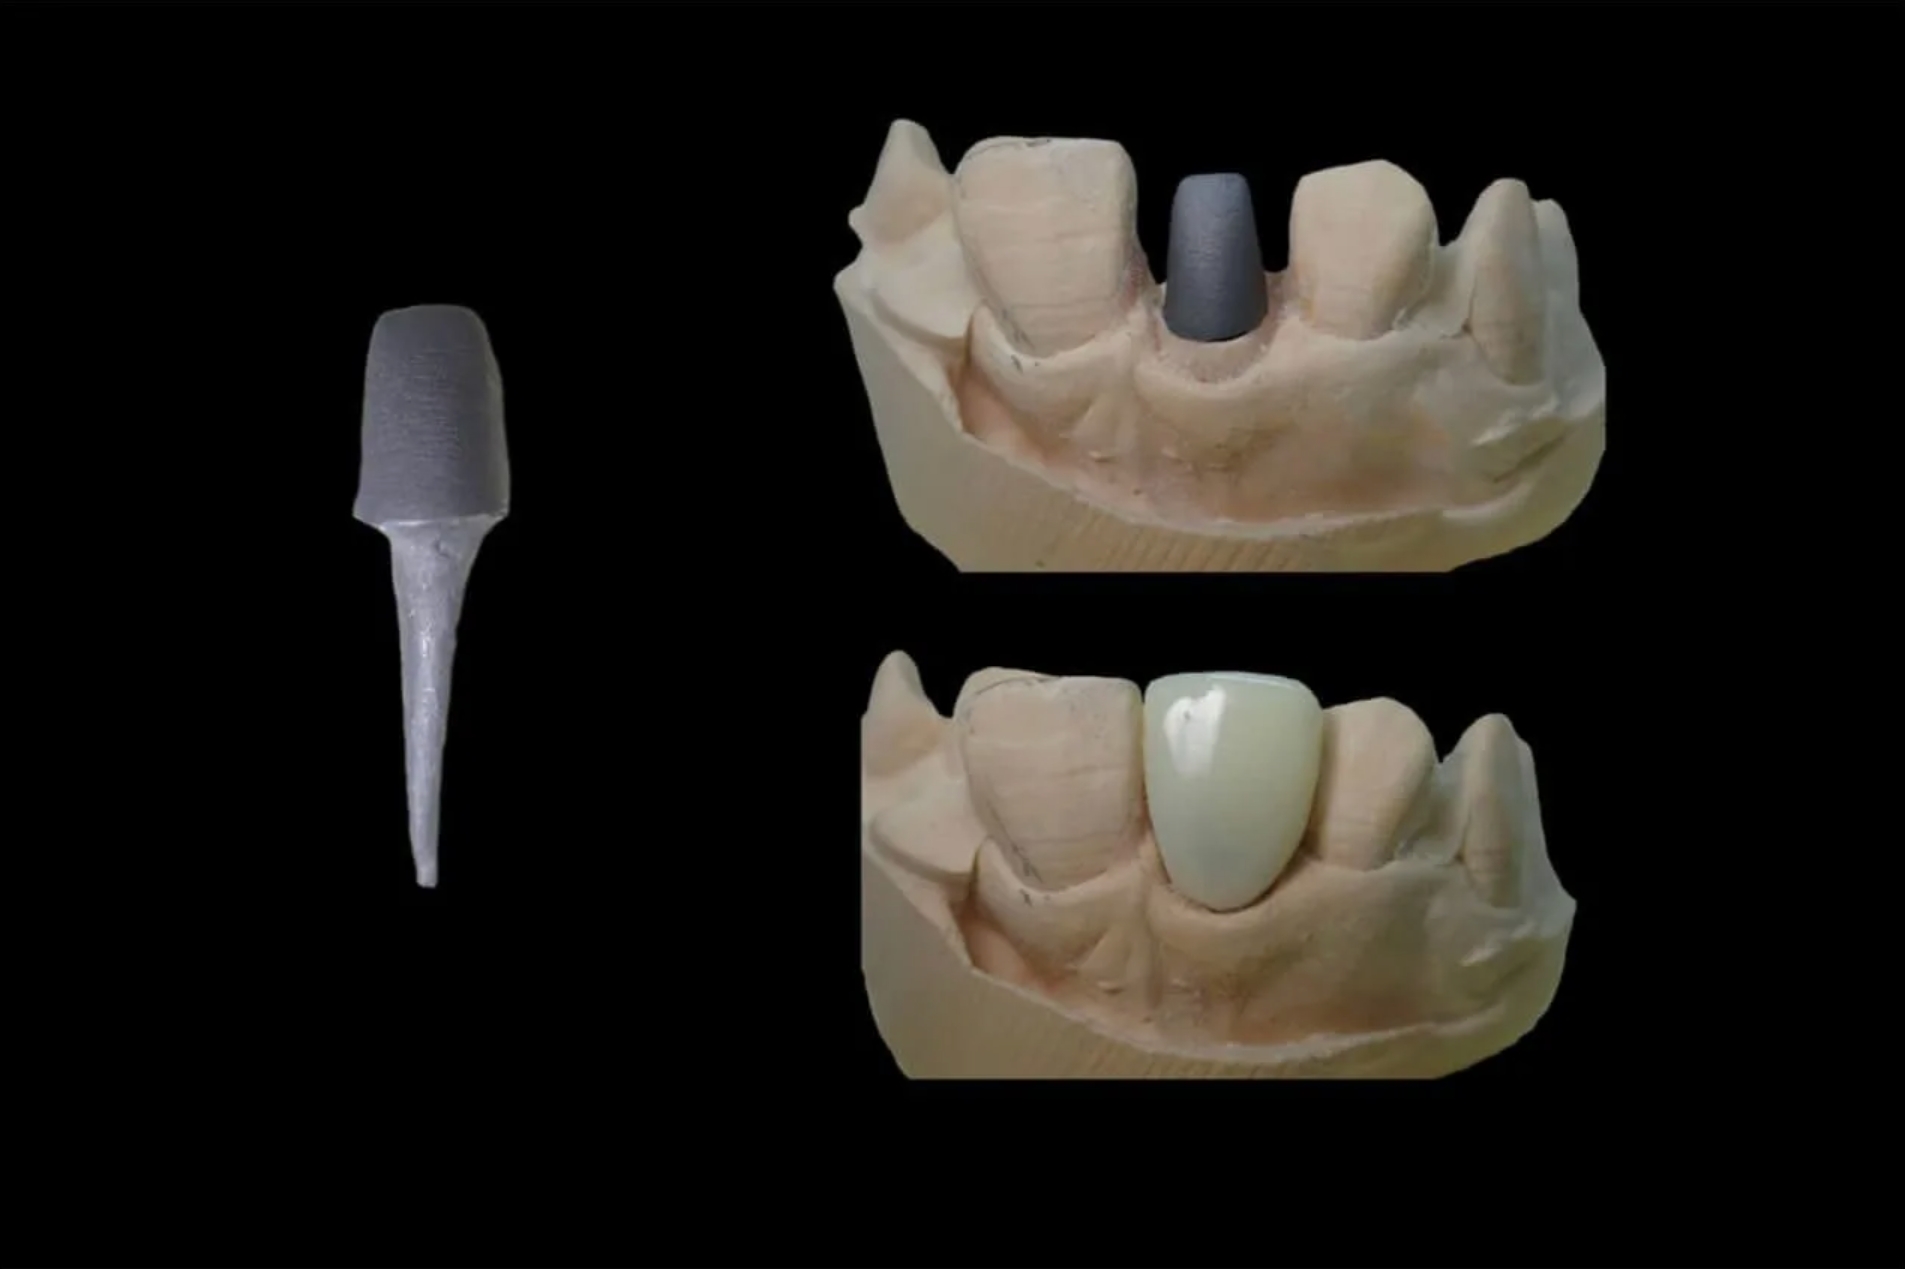

Культя зуба это

Культя зуба это 106 фото